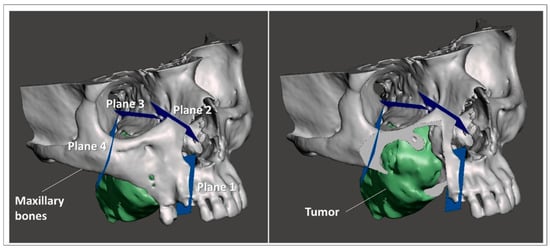

A 68-year-old patient with recurrent squamous cell carcinoma of the right maxilla. The patient was studied with a contrast-enhanced CT scan and MRI of head and neck, which showed an uptake of the dye at the level of a neoformation that infiltrated the right maxillary bone and its sinus, and probably extended to the ipsilateral mandibular branch (Figure 1).

Figure 1. (a) Intraoral view of the tumor; (b) preoperative RMN and CT scan, coronal slices.

Anatomical areas of interest for the surgery were segmented using D2P™ software (3D Systems Inc., Rock Hill, SC, USA), a certified software package designed to convert DICOM medical images into 3D digital models. In detail, the maxillary bones, the tumoral mass in the midface region and the facial skin were segmented as separated masks from the CT scan. Then, three-dimensional polygonal surface meshes were generated from each segmented mask and saved in STL (Standard Tessellation Language) format.

Using a 3D modeling software (Meshmixer, Autodesk Inc., San Rafael, CA, USA) virtual planes for maxillary bone resections were planned following the indications of maxillofacial surgeons, and then converted in STL objects (Figure 3).

Figure 3. Virtual planes for maxillary bone resections.